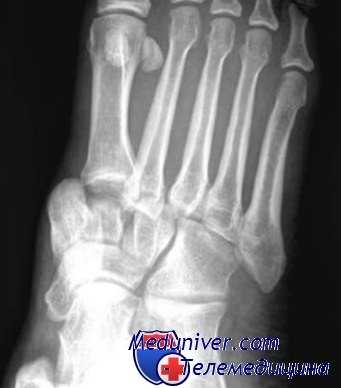

Переломы плюсневых костей

Переломы плюсневых костей по частоте занимают первое место среди всех переломов костей стопы. Обычно возникают при прямом воздействии травмирующей силы (сдавление стопы, падение тяжести или переезд стопы колесом). Могут быть множественными или одиночными. В зависимости от уровня повреждения выделяют переломы головки, шейки и тела плюсневых костей.

При одиночных переломах плюсневых костей выявляется локальный отек на тыле и подошве, боль при опоре и прощупывании. Множественные переломы плюсневых костей сопровождаются выраженным отеком всей стопы, кровоизлияниями, болью при пальпации. Опора затруднена или невозможна из-за боли. Возможна деформация стопы. Диагноз подтверждается данными рентгенографии в 2-х проекциях, а при переломах основания костей плюсны – в 3-х проекциях.

При переломах костей плюсны без смещения накладывают заднюю гипсовую шину сроком на 3-4 недели. При переломах со смещением проводят закрытое вправление, выполняют открытый остеосинтез или накладывают скелетное вытяжение. Срок фиксации при таких переломах костей стопы удлиняется до 6 недель. Затем пациенту накладывают специальную гипсовую повязку «с каблучком», а в последующем рекомендуют использовать ортопедические вкладки.

Изолированные, с небольшим смещением или без смещения переломы плюсневых костей лечатся консервативным способом. Рекомендуется плотная обувь с устойчивой подошвой, ортез или гипсовая повязка для надежности. Нагрузка на ногу определяется индивидуальной переносимостью. При переломах со смещением и вывихах в среднем отделе стопы показано анатомичное вправление, которое лучше выполнить открытым способом.